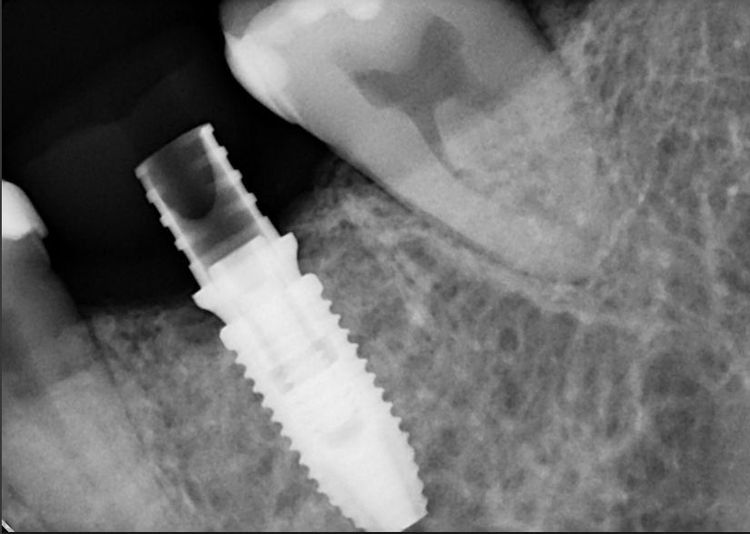

Через два месяца, после оценки состояния тканей, была выполнена установка дентального имплантата системы Nobel Biocare. Одновременно была проведена мягкотканевая пластика с целью улучшения анатомии будущей коронковой зоны. На имплантат установлен формирователь десны — временный компонент, необходимый для создания физиологического и эстетически благоприятного профиля прорезывания.